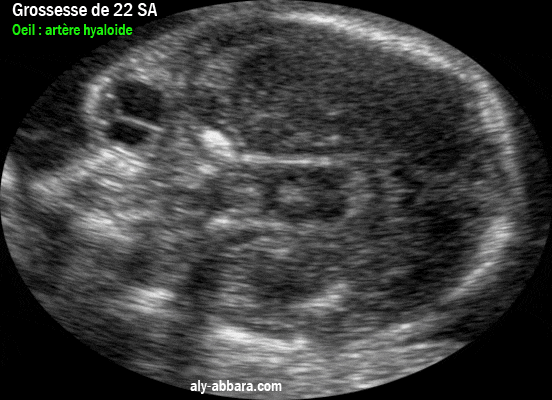

Image échographique prise à 22 SA de grossesse et mettant en évidence, sur une coupe transversale du l'oeil, le reliquat de l'artère hyaloïde

Image échographique prise à 22 SA de grossesse et mettant en évidence, sur une coupe transversale du l'œil droit, le reliquat de l'artère hyaloïde (ou hyaloïdienne).

• Échographiquement, l'artère hyaloïde apparaît vers la 18e semaine d'aménorrhée et disparaît normalement vers la 32e semaine d'aménorrhée.